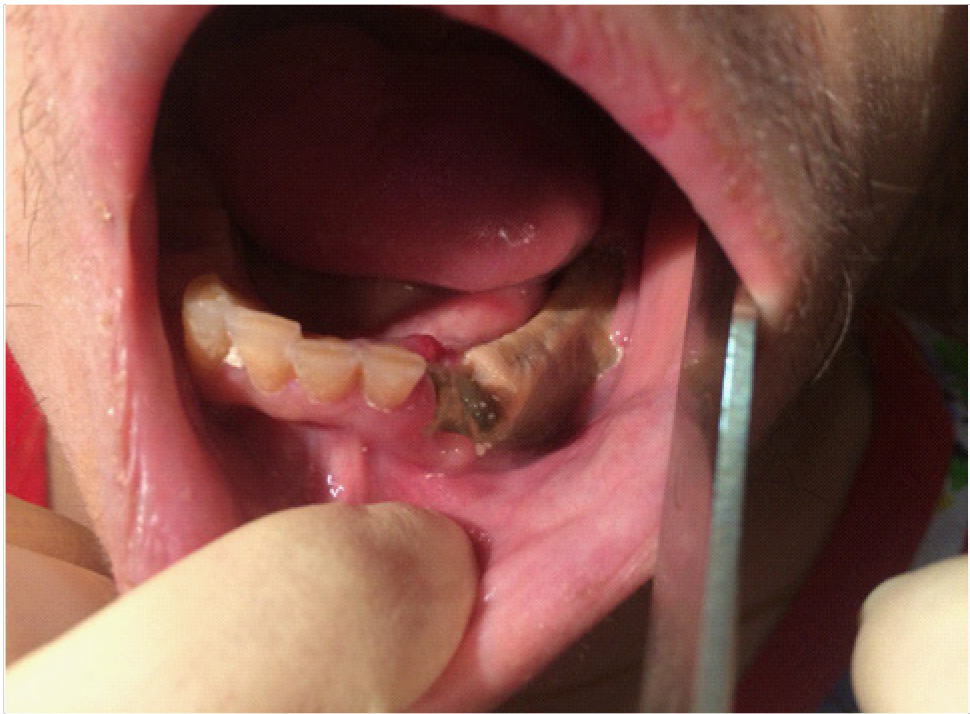

Пациент Р., 82 года, обратился в кабинет хирургической стоматологии с жалобами на острый край нижней челюсти. В ходе осмотра полости рта обнаружено нарушение целостности слизистой оболочки с субтотальным остеонекрозом альвеолярной части нижней челюсти во фронтальном отделе.

В полости рта: нарушение целостности слизистой оболочки полости рта, субтотальный остеонекроз альвеолярной части нижней челюсти слева. Вид костной тканей серо-коричневого цвета, пальпация безболезненная. На ортопантомограмме отмечается ограниченный участок деструкции костной ткани нижней челюсти с поражением тела нижней челюсти. Одонтогенной причины заболевания нет (рис. 1).

Рис. 1. Клинические проявления бисфосфонатного остеонекроза нижней челюсти во фронтальном отделе